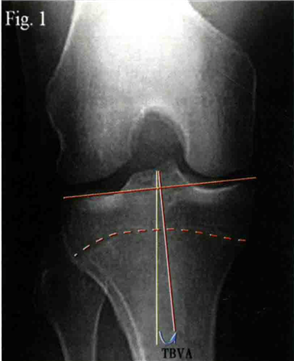

膝关节骨关节炎是指多种原因引起的关节软骨退化剥脱、关节周围韧带功能不全、关节周围骨性增生等情况,进而产生的一些列慢性疼痛和功能障碍。人类的膝关节自然状态下胫骨平台向内有着3º的倾斜,并且下肢的力学轴线通常处于膝关节中心偏内侧,单足站立时70%的负荷处于内侧间室。同时亚洲人群和南地中海人群往往有着较大的胫骨内翻角(TBVA),所以在中国,超过60%的膝关节骨关节炎病人的病变仅仅累及内侧间室。

左:下肢力线与膝关节关节线的夹角,平均内倾3º

右:胫骨内翻角(TBVA):胫骨干骺端连线中点与胫骨髁间嵴中心的连线a,胫骨力学轴线b,a与b的夹角即为TBVA角。它不受胫骨平台关节磨损影响,可评估膝关节内翻程度和判断HTO预后